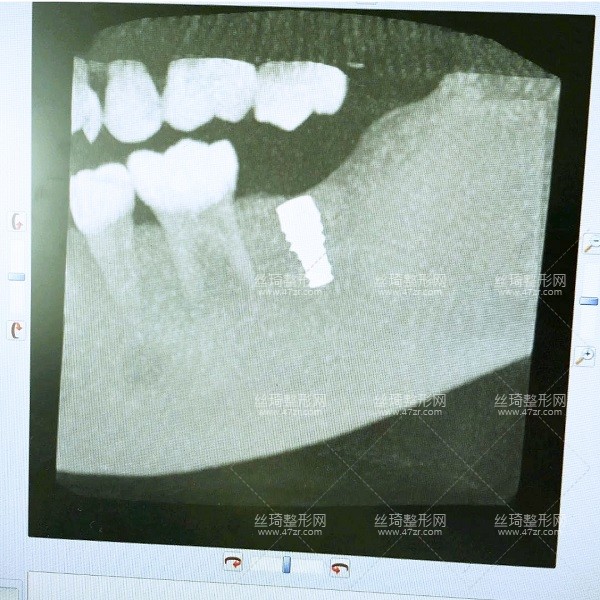

2.種植牙案例

手術(shù)第1天

一直不知道什么原因?qū)е挛业难罆@樣,多方咨詢之后選擇了長沙中諾口腔進行整牙,過去檢查了一下,醫(yī)生說我可以搞種植牙,但是以前補過的牙現(xiàn)在顏色變了,需要重新做,看來是個大工程啊,啊啊啊啊~~~

手術(shù)第2天

今天過來醫(yī)生檢查了我的牙床和骨組織,情況不錯,可以直接調(diào)節(jié)。首先助理幫我清潔口腔,護士準備手術(shù)室,清理過口腔后,吃了止痛藥,然后進手術(shù)室,然后躺到牙椅上,就打麻藥的時候有點緊張,種牙很輕松,全程一個半小時。出來后,冰敷了,告訴我注意事項,讓我一周后來拆線。